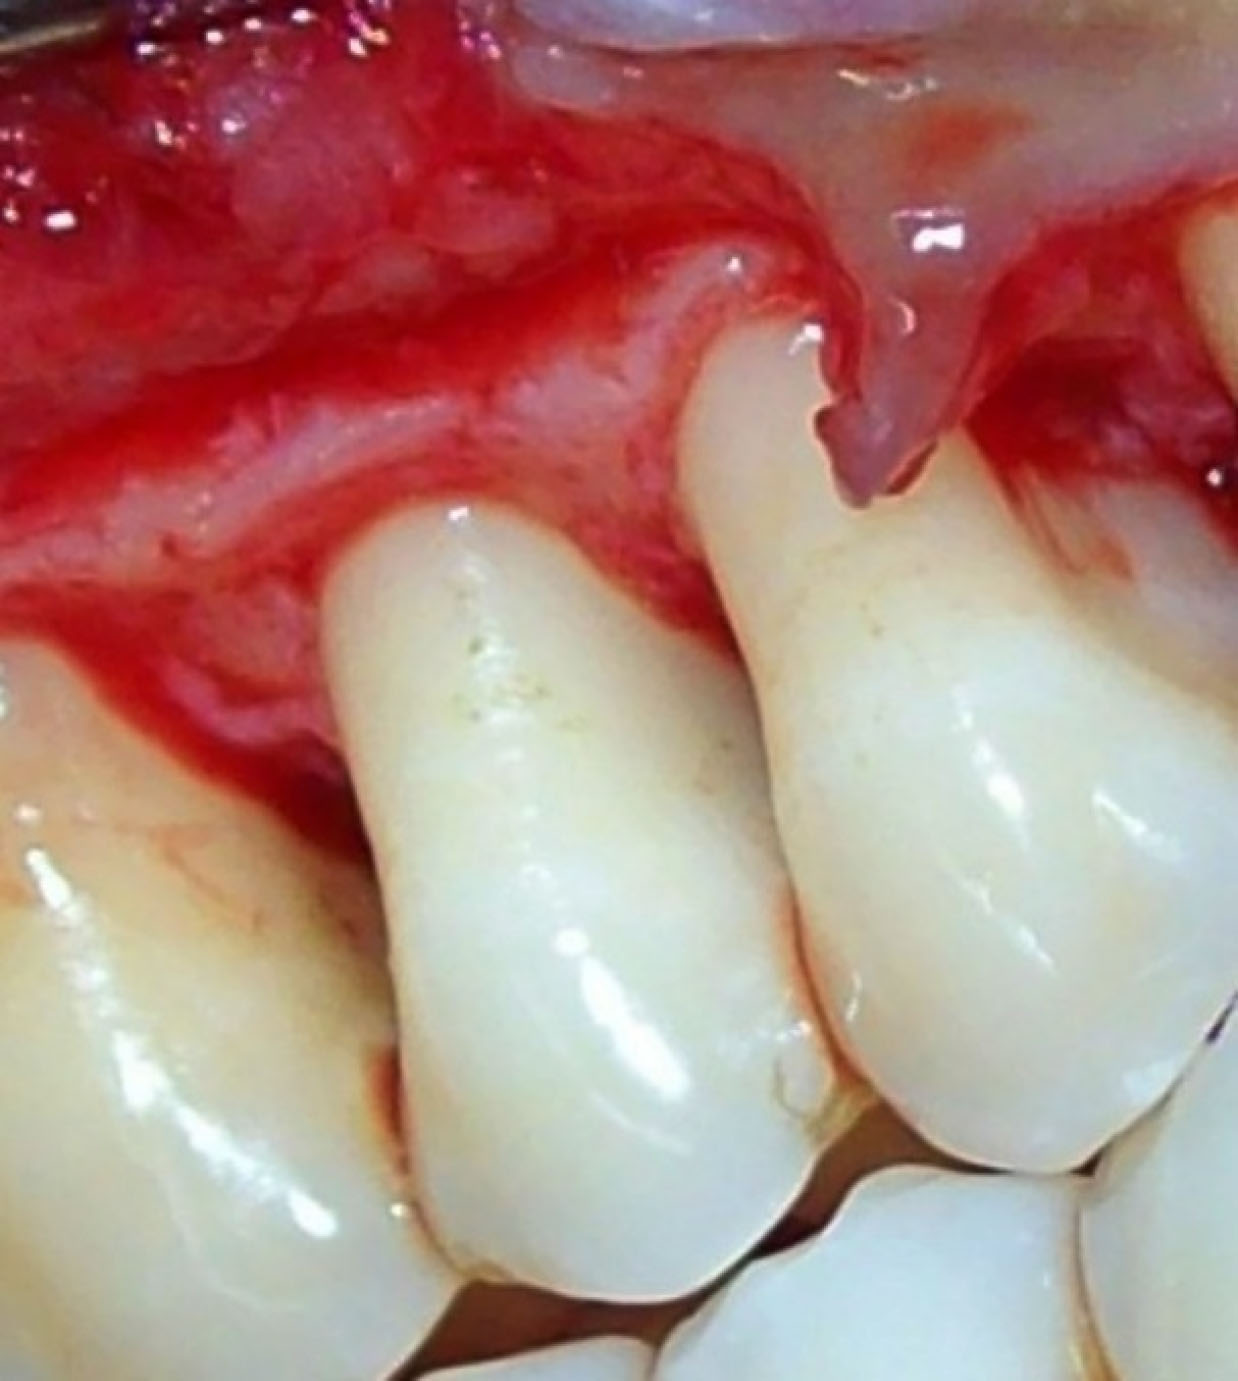

Figure 3. Flap reflection and debridement; the control group.

Control sites ( and ) were treated with MWF and sham application of DL therapy, whereas test sites underwent MWF and active DL application. In all the sites, the MWF was followed by SRP and elimination of granulation tissue using hand and power-driven instruments. Before each irradiation episode, a power meter (Fieldmaster, Coherent, Alburn, USA) was used, which allowed the adjustment and standardization of the amount of energy used. For test sites, a DL (wavelength = 940 nm, power = 1 W, tip diameter = 400 µm, power density = 796 W/cm2) was used in continuous mode to remove visible epithelium from the undersurface of the flap. The DL irradiation was carried out at a 45º angle to the soft tissue for 10 seconds from the coronal to apical aspect in parallel paths, followed by 30 seconds of interruption. The charing layer, which was produced due to laser application, was removed with moist gauze. A second laser application (LLLT) was carried out on all the surfaces of the flap (under and outer, exposed bone, and exposed root structures) in continuous mode at 0.1 W, adding up to a total dose of 4 J/cm2 per surface (). The flaps were sutured with 3-0 black silk sutures. Ibuprofen with a 200-mg dose was prescribed every eight hours for five days for pain control. Furthermore, patients were requested to avoid brushing in the treated area for two weeks. They resumed full oral hygiene and function after two weeks.